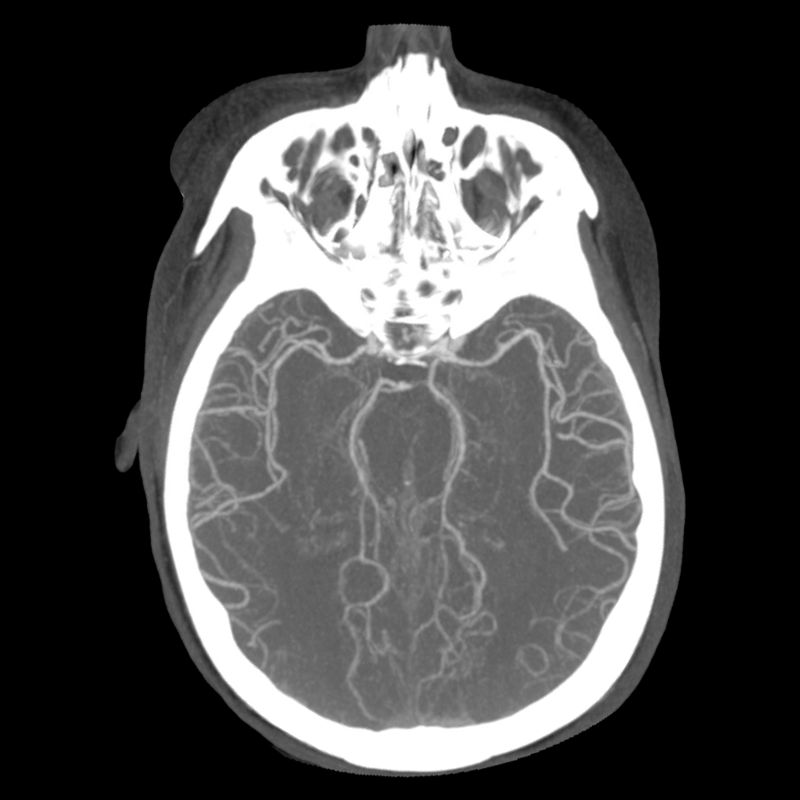

CTA part 1 CTA part 2 CTA part 3

The non-contrast head CT looks generally similar to her prior scan. There's no new hemorrhage anywhere. There's no mass effect causing midbrain compression. The vessel imaging also looks unrevealing-- a slightly hypoplastic right A1 segment, but no clear LVO in either the anterior or posterior circulation. There's no vasoconstriction.